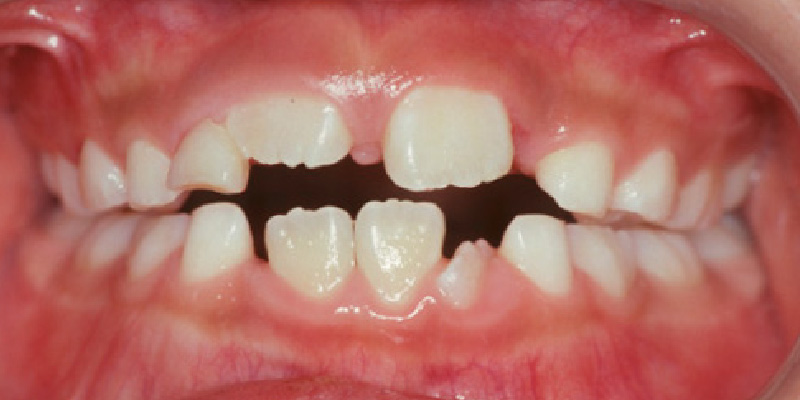

スプリント後

[1年6か月のスプリント療法後]

【お顔】オトガイの左側への変位は改善し、目立たなくなりました。【口腔内】正中はほぼ一致し、開咬も改善しました。

行なったのは顎位安定型のスプリント装着のみで、個別の歯の移動は行なっていません。このように環境を良くして正常な成長を促します。 2次治療開始までスプリント装着を(時間を減らして)継続します。